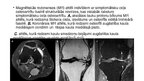

Osteoartrīts, arī osteoartroze ir locītavu slimības veids. Izraisa locītavu virsmu skrimšļu nodilumu un sekojošus bojājumus

Biežākie simptomi ir locītavu sāpes un stīvums. Sākumā tie var parādīties pēc fiziskām aktivitātēm, tomēr ar laiku simptomi var būt pastāvīgi. Vēl var būt locītavu pietūkums, ierobežota kustības spēja; gadījumos, kad tiek ietekmēta mugura, var būt roku un kāju vājums vai nejutīgums. Visbiežāk slimība skar pirkstu galu, īkšķa pamatnes, kakla, muguras, ceļgalu un gurnu

locītavas. Biežāk tiek skartas locītavas vienā ķermeņa pusē, nekā tās pašas otrā pusē. Problēmas parasti rodas gadu gaitā. Atšķirībā no citu veidu artrītiem, osteoartrīts parasti skar vienīgi locītavas.…